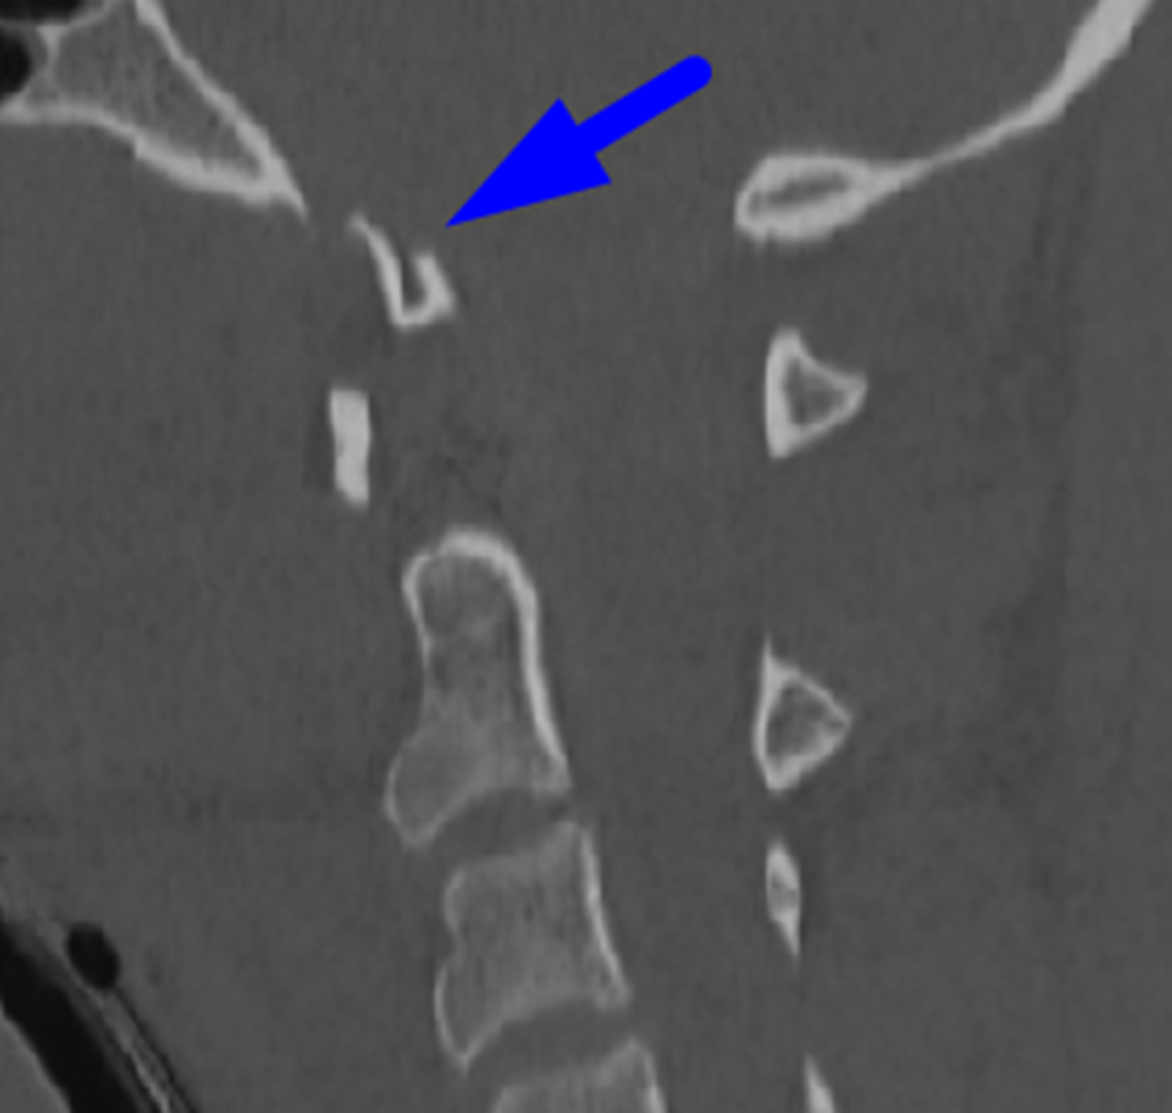

Blue arrow: displaced occipital condyle fracture.